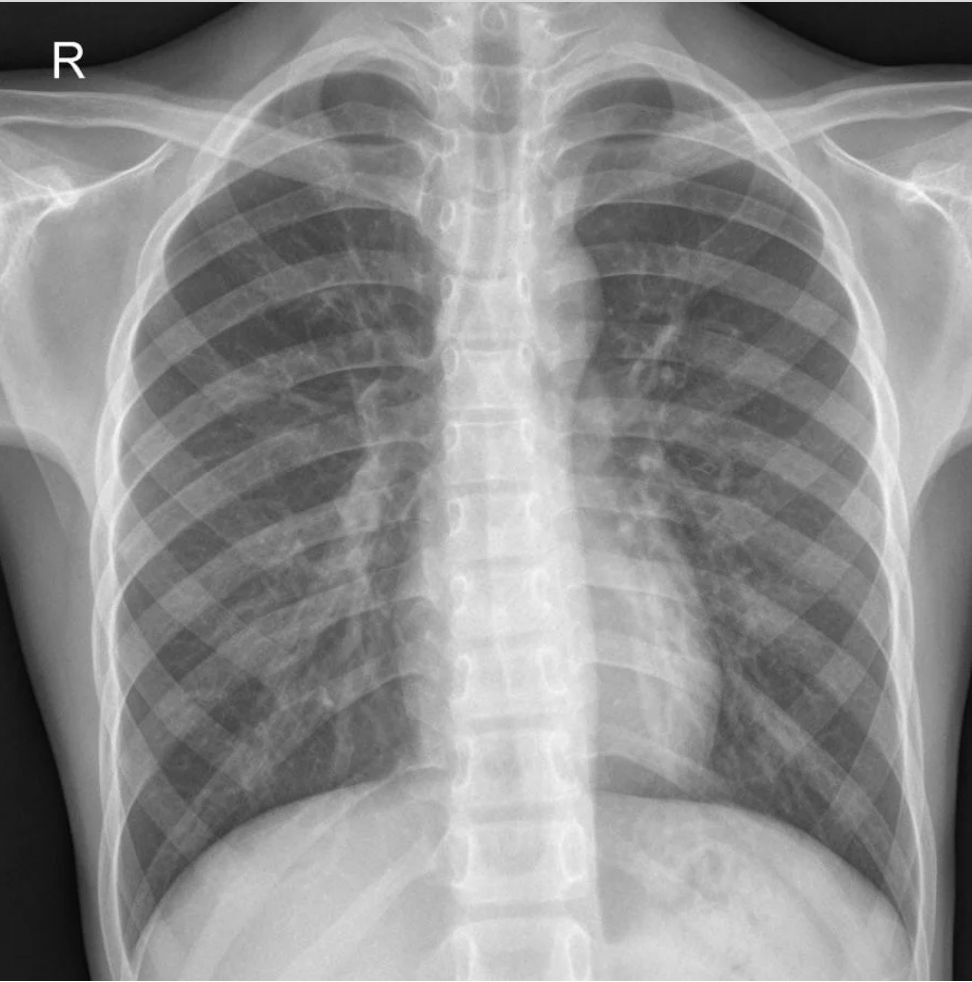

1. An 63 year old man has a heart arrhythmia. Upon further investigation, an angiogram shows an occlusion of the proximal right coronary artery. Why would this potentially cause arrhythmia? Discuss the anatomy and relationships of the right coronary artery and branches as well as the complementary venous drainage. Include mention of any commonly seen anatomical variances, if any.

2. A patient is shown to have a partial occlusion of their anterior interventricular artery (left anterior descending artery). Discuss the anatomy and relationships of the left coronary artery and branches as well as the complementary venous drainage. Why is an occlusion in this artery especially dangerous and what potential surgical solutions can be used as treatment? Include mention of commonly seen anatomical variances, if any.